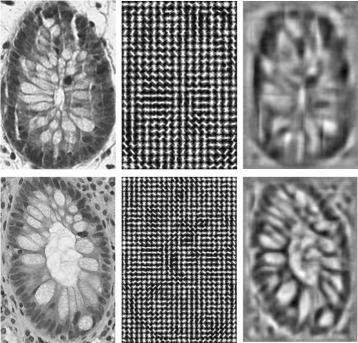

A seeding-searching-ensemble method for gland segmentation in H&E-stained images.

In this paper, we develop a new approach for segmenting and detecting intestinal glands in H&E-stained histology images, which utilizes a set of advanced image processing techniques: graph search, ensemble, feature extraction, and classification. Our method is computationally fast, preserves gland boundaries robustly and detects glands accurately.

We tested the performance of our gland detection and segmentation method by analyzing a dataset of over 1700 glands in digitized high resolution clinical histology images obtained from normal and diseased human intestines. The experimental results show that our method outperforms considerably the state-of-the-art methods for gland segmentation and detection.